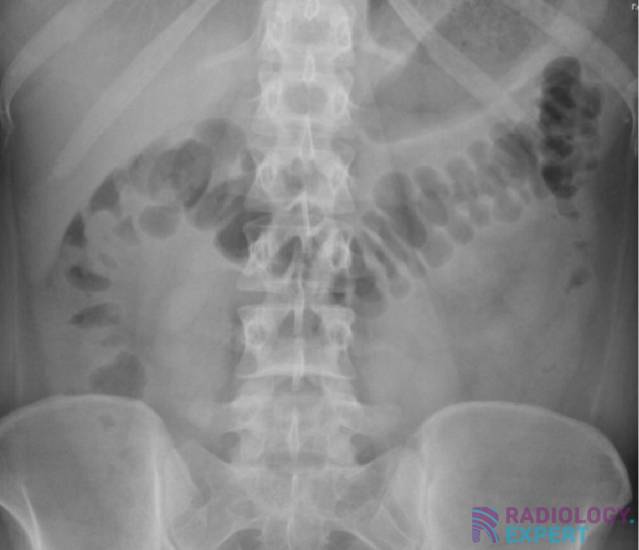

Abdominal X-ray

The basic principles of the abdominal X-ray examination.

Although the abdominal X-ray is performed less frequently these days, it still has clinical value in certain situations. Some knowledge about this research is therefore essential.

Some of the key topics are volvulus, free air and nephrocalcinosis.

• Ileus

• Sigmoïd volvulus

• Cecal volvulus

• Free air

• Nephrolithiasis

• Urolithiasis

• Nephrocalcinosis

• Foreign body